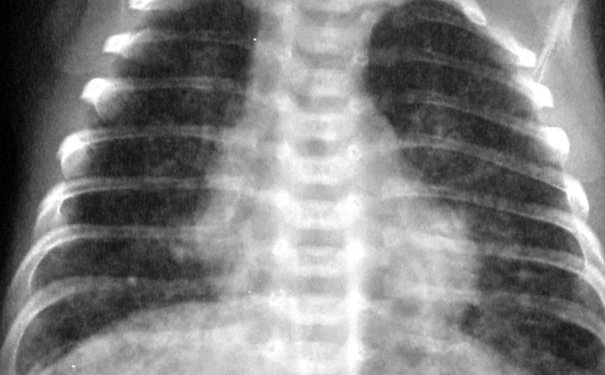

在进行胸透的时候,很多人都会发现肺部有阴影,这导致很多人的心都悬起来了,因为在我们的常识中,阴影代表着癌症,其实并不是这样的,还可能是由于其他疾病导致的阴影,那么肺部有阴影是怎么回事呢?肺上有阴影回事什么病呢?

如果肺部有阴影可能是感染了肺炎,肺炎是病源微生物(细菌、支原体、衣原体、病毒等)引起的肺部感染,除了X线检查有肺部阴影外,患者还有咳嗽、咳痰、发烧、胸闷、乏力、呼吸困难等症状,严重者甚至可以发生感染中毒性休克。

如果肺部有阴影则可能患有肺结核,肺结核是由一种特殊的细菌,也就是结核杆菌造成的肺部感染常见部位是两侧上肺的尖、后段和下叶的背段,阴影表现为散在的片絮状,当中可以有钙化灶,有时可以是球形病灶或粟粒样病灶,极个别的可以累及一侧整个肺叶,形成所谓的“毁损肺”。

如果肺部出现阴影也可能是支气管扩张引起的,支气管扩张是支气管壁的化脓可爱染造成的支气管腔的扩大,是一种不可逆性的感染。X线胸片表现为肺纹理增多、增粗、紊乱,严重的支气管扩张可以表现为串珠样小透亮区,呈典型的蜂窝样阴影。常见的症状是长期咳脓痰和咳血。

肺部有阴影可能是肺囊肿,肺囊肿又叫先天性支气管肺囊肿,多见于男性儿童和青壮年,特点是远端支气管的先天性畸形,分为单发性和多发性。X线胸片表现为单个或多个圆形薄壁阴影,边缘清楚,如果囊肿和支气管相通,就会在阴影中发现气液平面。一般肺囊肿可长期无症状,往往在X线查体时偶然发现。